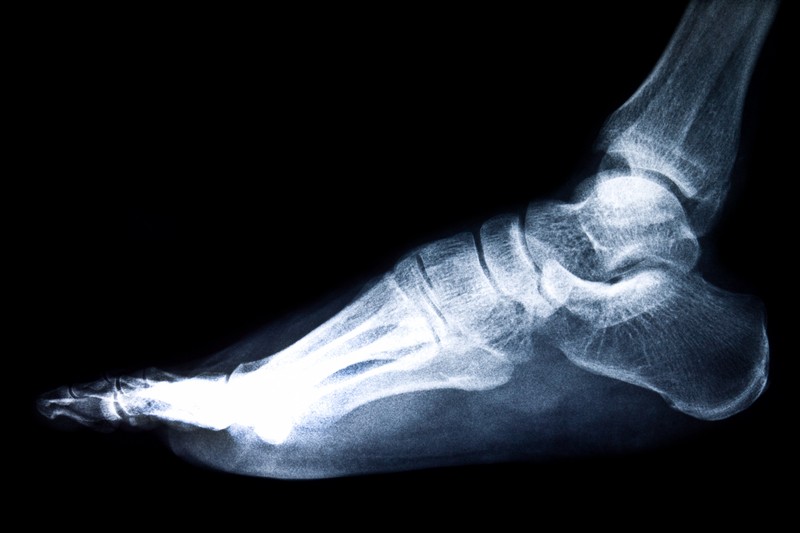

В большинстве случаев хондромы встречаются в костях, особенно в длинных трубчатых костях, таких как бедренная или плечевая кости. На начальных этапах своего развития данная патология никак не показывает своих симптомов и может выявляться случайно при рентгенографии.

Для выявления хондромы проводят следующие обследования.

Следует подчеркнуть, что ранняя диагностика хондромы имеет ключевое значение для выбора адекватного лечения и улучшения прогноза для пациента.